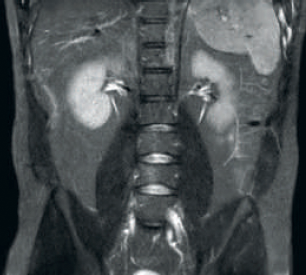

Resultado: resolución de imagen y SNR mejoradas

Mayor consistencia y mejor calidad de imagen La tecnología de recepción de RF dStream digitaliza la señal del RM directamente en la bobina de radiofrecuencia, lo que resulta en un aumento de hasta un 40 % más de la SNR* en todo el volumen de la imagen. Flujo de trabajo simplificado y rendimiento mejorado La bobina posterior integrada en la mesa elimina el manejo de la bobina en el 60 % de los exámenes. Las ligeras bobinas anteriores conformadas y las conexiones de bobina de un solo cable y de una sola mano contribuyen a la facilidad operativa.